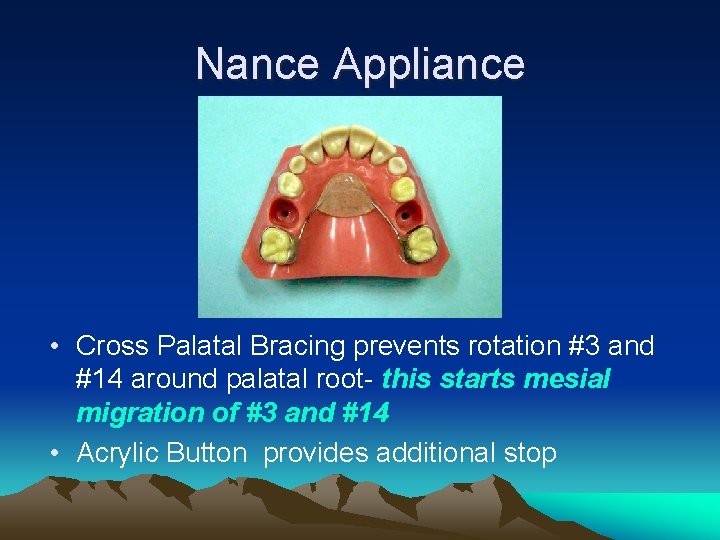

Nance Appliance • MAXILLARY ONLY • Bands on first permanent molars

Nance Appliance • Cross Palatal Bracing prevents rotation #3 and #14 around palatal root- this starts mesial migration of #3 and #14 • Acrylic Button provides additional stop